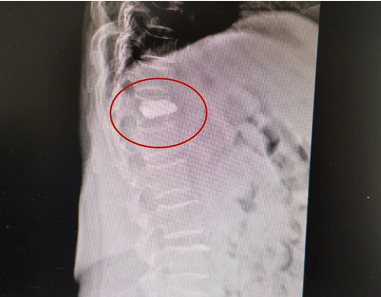

患者郭某,女,64岁,不慎摔倒,腰背部疼痛伴活动受限2天,休息后症状不见好转,就诊于我院脊柱科。X线片提示胸T12椎体压缩性骨折。完善术前相关检查后,来院第二天予患者行胸T12骨水泥椎体成形术,手术约30分钟后,患者自觉腰背部疼痛明显减轻。术后第二天拍片复查后,患者带腰围可下床自行活动。

患者骨水泥椎体成形术术前影像